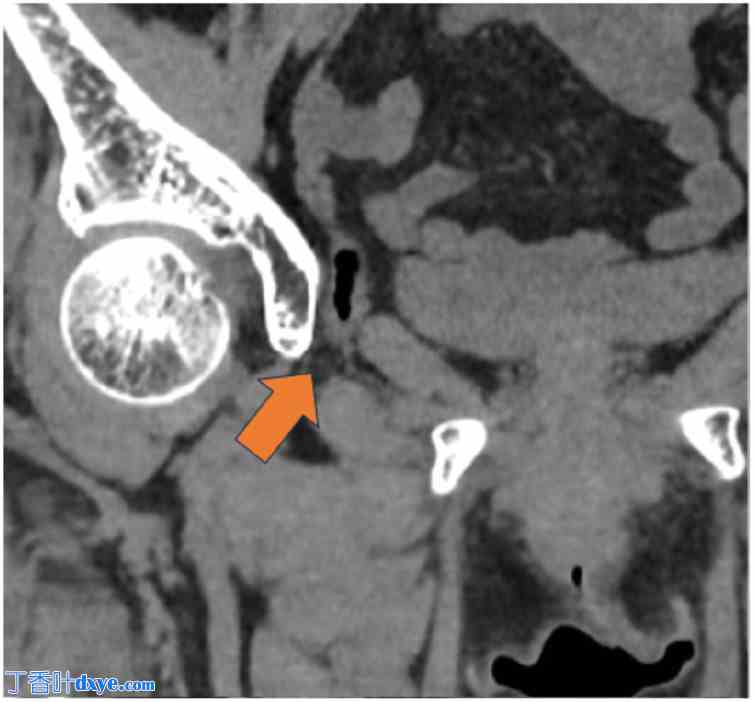

一名74岁女性被诊断为闭孔膀胱疝,并转诊至我科行手术治疗。该患者最初因便血入院,被诊断为缺血性结肠炎。诊断时进行的CT检查意外发现小肠闭孔疝(图1)。次日复查CT显示膀胱经闭孔疝出(图2)。因此,她随后被转诊至院进行进一步评估和治疗。她的缺血性结肠炎经保守治疗后痊愈。患者身高151.7 cm,体重45.3 kg,BMI为19.7。她没有与闭孔膀胱疝相关的症状。既往病史包括子宫肌瘤和阑尾炎,分别接受了腹腔镜下子宫肌瘤切除术和阑尾切除术。她不吸烟,偶尔饮酒。院CT检查证实膀胱经闭孔疝出,确诊为闭孔膀胱疝(图3)。在详细解释病情及相关风险后,患者同意接受手术治疗。

图3. 院的CT扫描。箭头:膀胱经闭孔疝出。

3.jpg